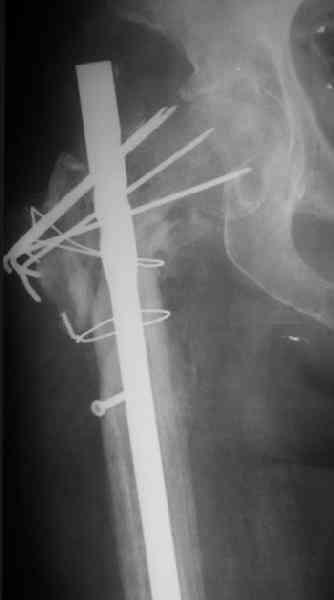

Поступила женщина 62 лет. В X 2006 оперировна в одной из горбольниц, по поводу, видимо, оскольчатого подвертельного перелома.

Почему сделан такой странный остеосинтез - пока неизвевстно. 3 мес. в тазобедренной гипсовой повязке. Картина через полгода после операци, в апреле - первый снимок. После этого снимка убрали винт, проникающий в сустав. Картина на сегодня - следующие 2 снимка.

Dear All,A female 62 y.o. referred to our unit. In X 2006 was operated somewhere - open reduction and fixation of a fragmented subtrochanteric fracture. Why so strange fixation was performed - no data at the moment. 3 month in plaster cast. Image 1 - Apr 2007, 6 month after the surgery. The screw was removed some days later.

Other images present the current situation.